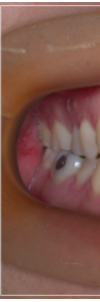

개방교합은 입을 다물때 안쪽

어금니만 맞닿고 앞니 쪽은 닿지 않아

입술이 붕 떠 있는 상태를 말했어요.

만일 이러한 개방교합이 턱관절 질환에

의해 발생하였을 경우 잘 모르고

치아 교정부터 진행하게 되면

턱이 불안정한 상태에서 무리하게

치아를 이동시키게 되기 때문에

오히려 질환을 악화시키거나

개방교합이 다시 재발하는 등 문제가

발생할 수 있어 주의가 필요했어요.